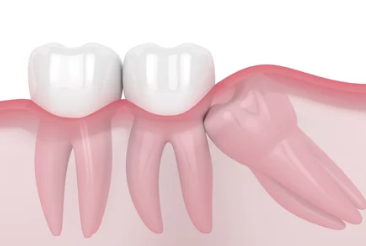

사랑니가 잇몸 아래에서 정상적으로 자라지 못하고, 잇몸 안이나 다른 치아에 눌려 비정상적인 방향으로 자라는 상태를 매복 사랑니라고 합니다. 매복의 정도는 다음과 같이 나뉩니다:

- 부분 매복: 사랑니 일부가 잇몸 밖으로 나와 있는 상태.

- 완전 매복: 사랑니가 완전히 잇몸 아래에 매복된 상태.